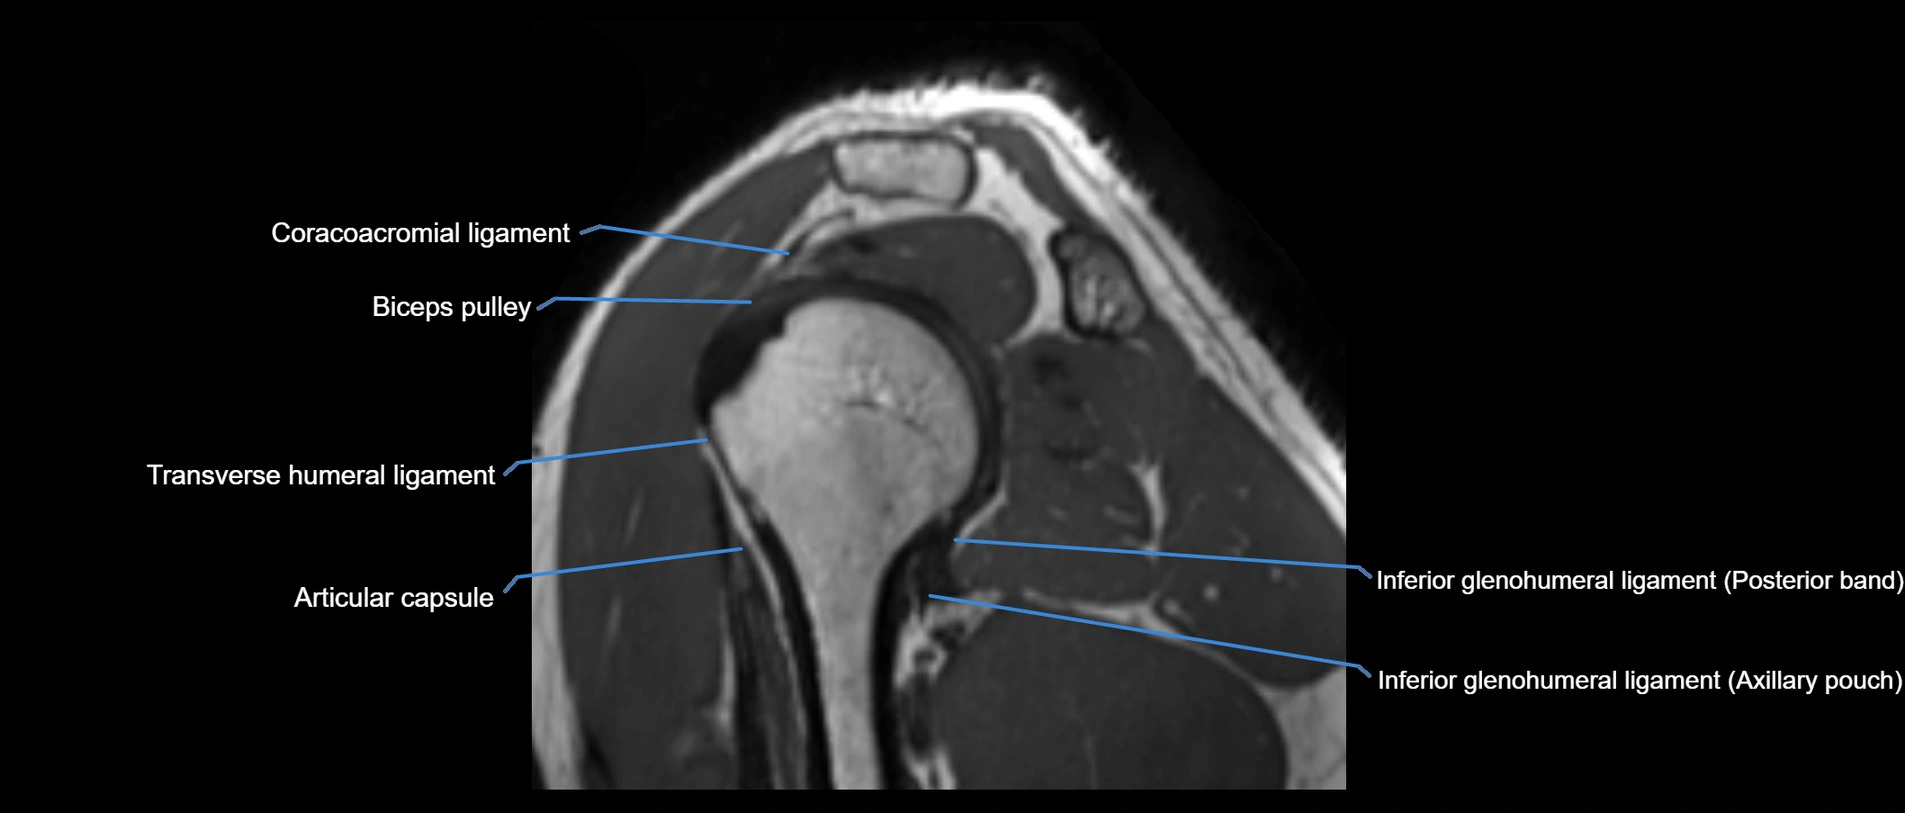

MRI images

image

CT image